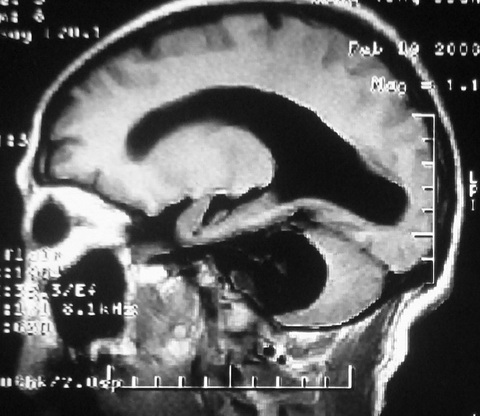

m,72,头疼,头晕两年,伴视力模糊三月,饮食呛咳两天。pe:颈部抵抗,左眼突出,左眼瞳孔约3mm,对光反射消失,双眼失明,伸舌困难,双肺呼吸音粗,心率110次/分,左上肢肌力i级,左下肢屈曲,肌张力高。现有08年2月19mri平扫及10年2月8日mri增强请会诊。ct病灶呈低密度伴散在点、片状等密度区,无明确钙化(无ct片资料可供上传)。[

左侧桥小脑区占位伴梗阻性脑积水----考虑 1神经鞘瘤 2室管膜瘤。

左侧桥小脑区神经鞘瘤伴梗阻性脑积水。

左侧桥脑小脑角区肿瘤并脑积水,考虑听神经瘤,脑膜瘤?

左侧桥脑小脑角区肿瘤并脑积水,考虑听神经瘤,